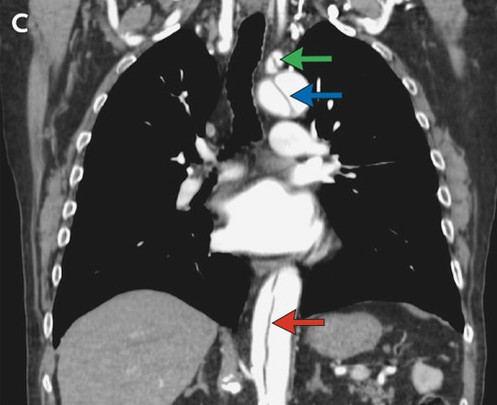

胸腹部CT血管成像示升主动脉瘤(图A,蓝色箭头),DeBakey I型主动脉夹层动脉瘤。该夹层涉及了升主动脉(图B,白色箭头),主动脉弓(图C,蓝色箭头),以及降主动脉(图B、C,红色箭头),结束于肾动脉起点之下。同时还涉及了几条血管分支,包括右头臂动脉、左锁骨下动脉(图C,绿色箭头)和肠系膜上动脉。